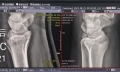

成人非创伤性股骨头缺血性坏死分期法评价_介绍一种新的国际分期方法